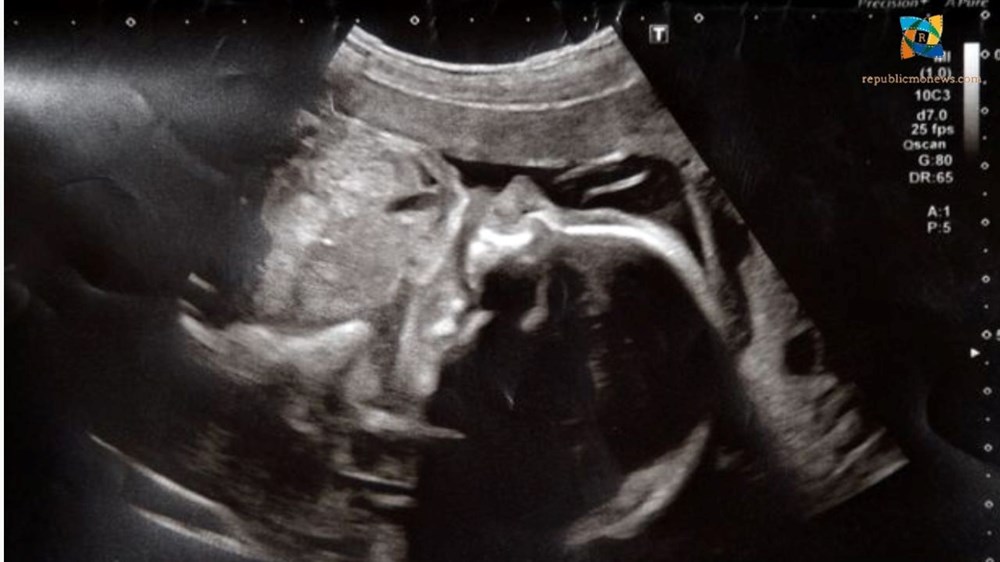

27 yaşındaki Hannah Cole adlı İngiliz kadın, 20 haftalık hamileyken suyu geldikten sonra Bradford Kraliyet Hastanesine (BRI) kabul edildi. Doktorlar ertesi gün bebeğinin kalp atışının tespit edilmediğini ve anne karnında öldüğünü söyledi.

Ancak oğlunun hala hayatta olduğuna dair bir 'içgüdü', Cole’u hastaneden son bir tarama istemeye teşvik etti ve o zaman doktorlar tekrar kalp atışı buldu. Oakley Cole-Fowler adlı bebek nihayet 24 hafta ve üç günlükken 30 Ekim'de sadece 780 gram olarak dünyaya geldi.